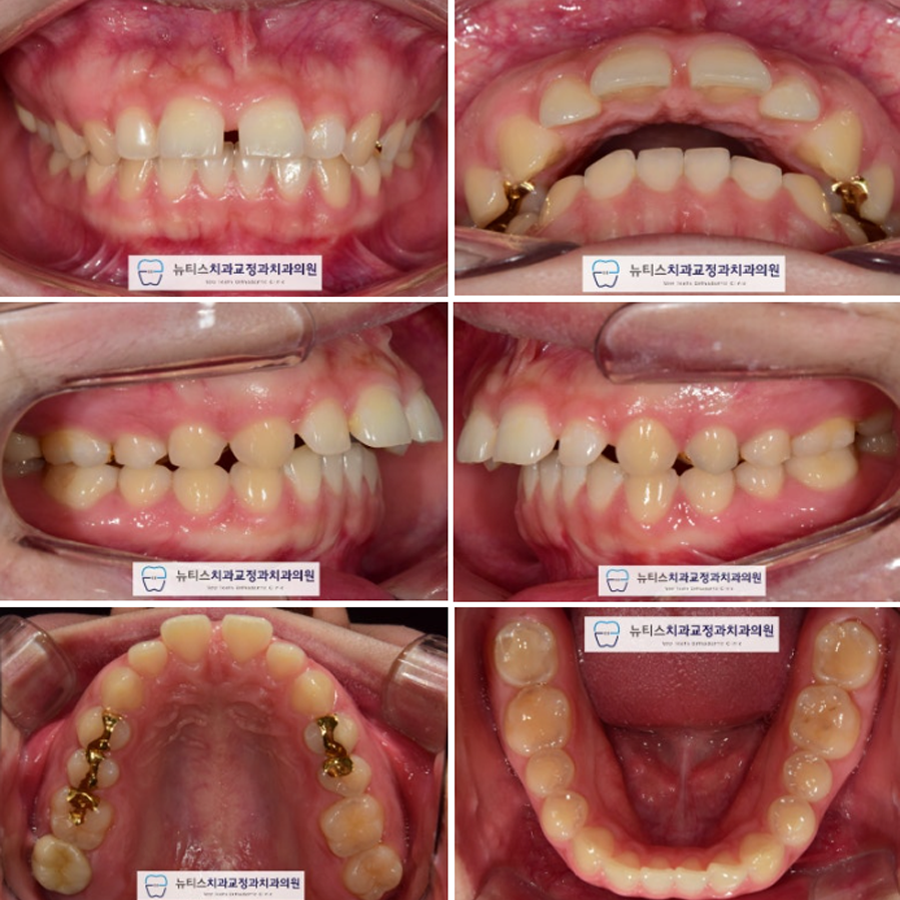

ÃÊÁø »çÁøÀÔ´Ï´Ù.

¾Æ·¡ Ä¡¾Æ¿¡ ºñÇØ ¾ÕÀ¸·Î µ¹ÃâµÈ

»ó¾Ç Ä¡¾Æ¸¦ º¸ÀÔ´Ï´Ù.

¶ÇÇÑ ÀÌ·Î ÀÎÇØ ±¸¼øµ¹Ãâ°¨À» ³ªÅ¸³»°í ÀÖÀ¸¸ç

Ãø¸é»ó¿¡¼ º¸¸é ±³ÇÕÀÌ ¸ÂÁö ¾ÊÀ½À» ¾Ë ¼ö ÀÖ½À´Ï´Ù.